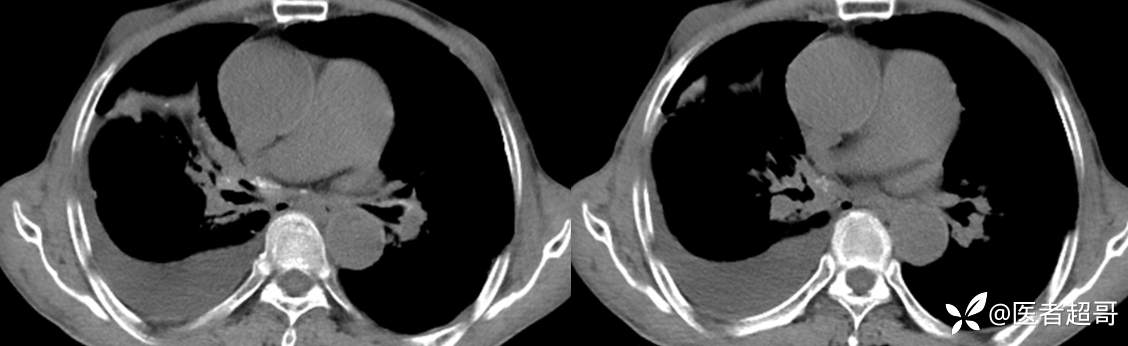

患者,男,72岁,农民,于2021年05月26日17时20分因"发作性精神行为异常10+天"入院。@丁香影像频道